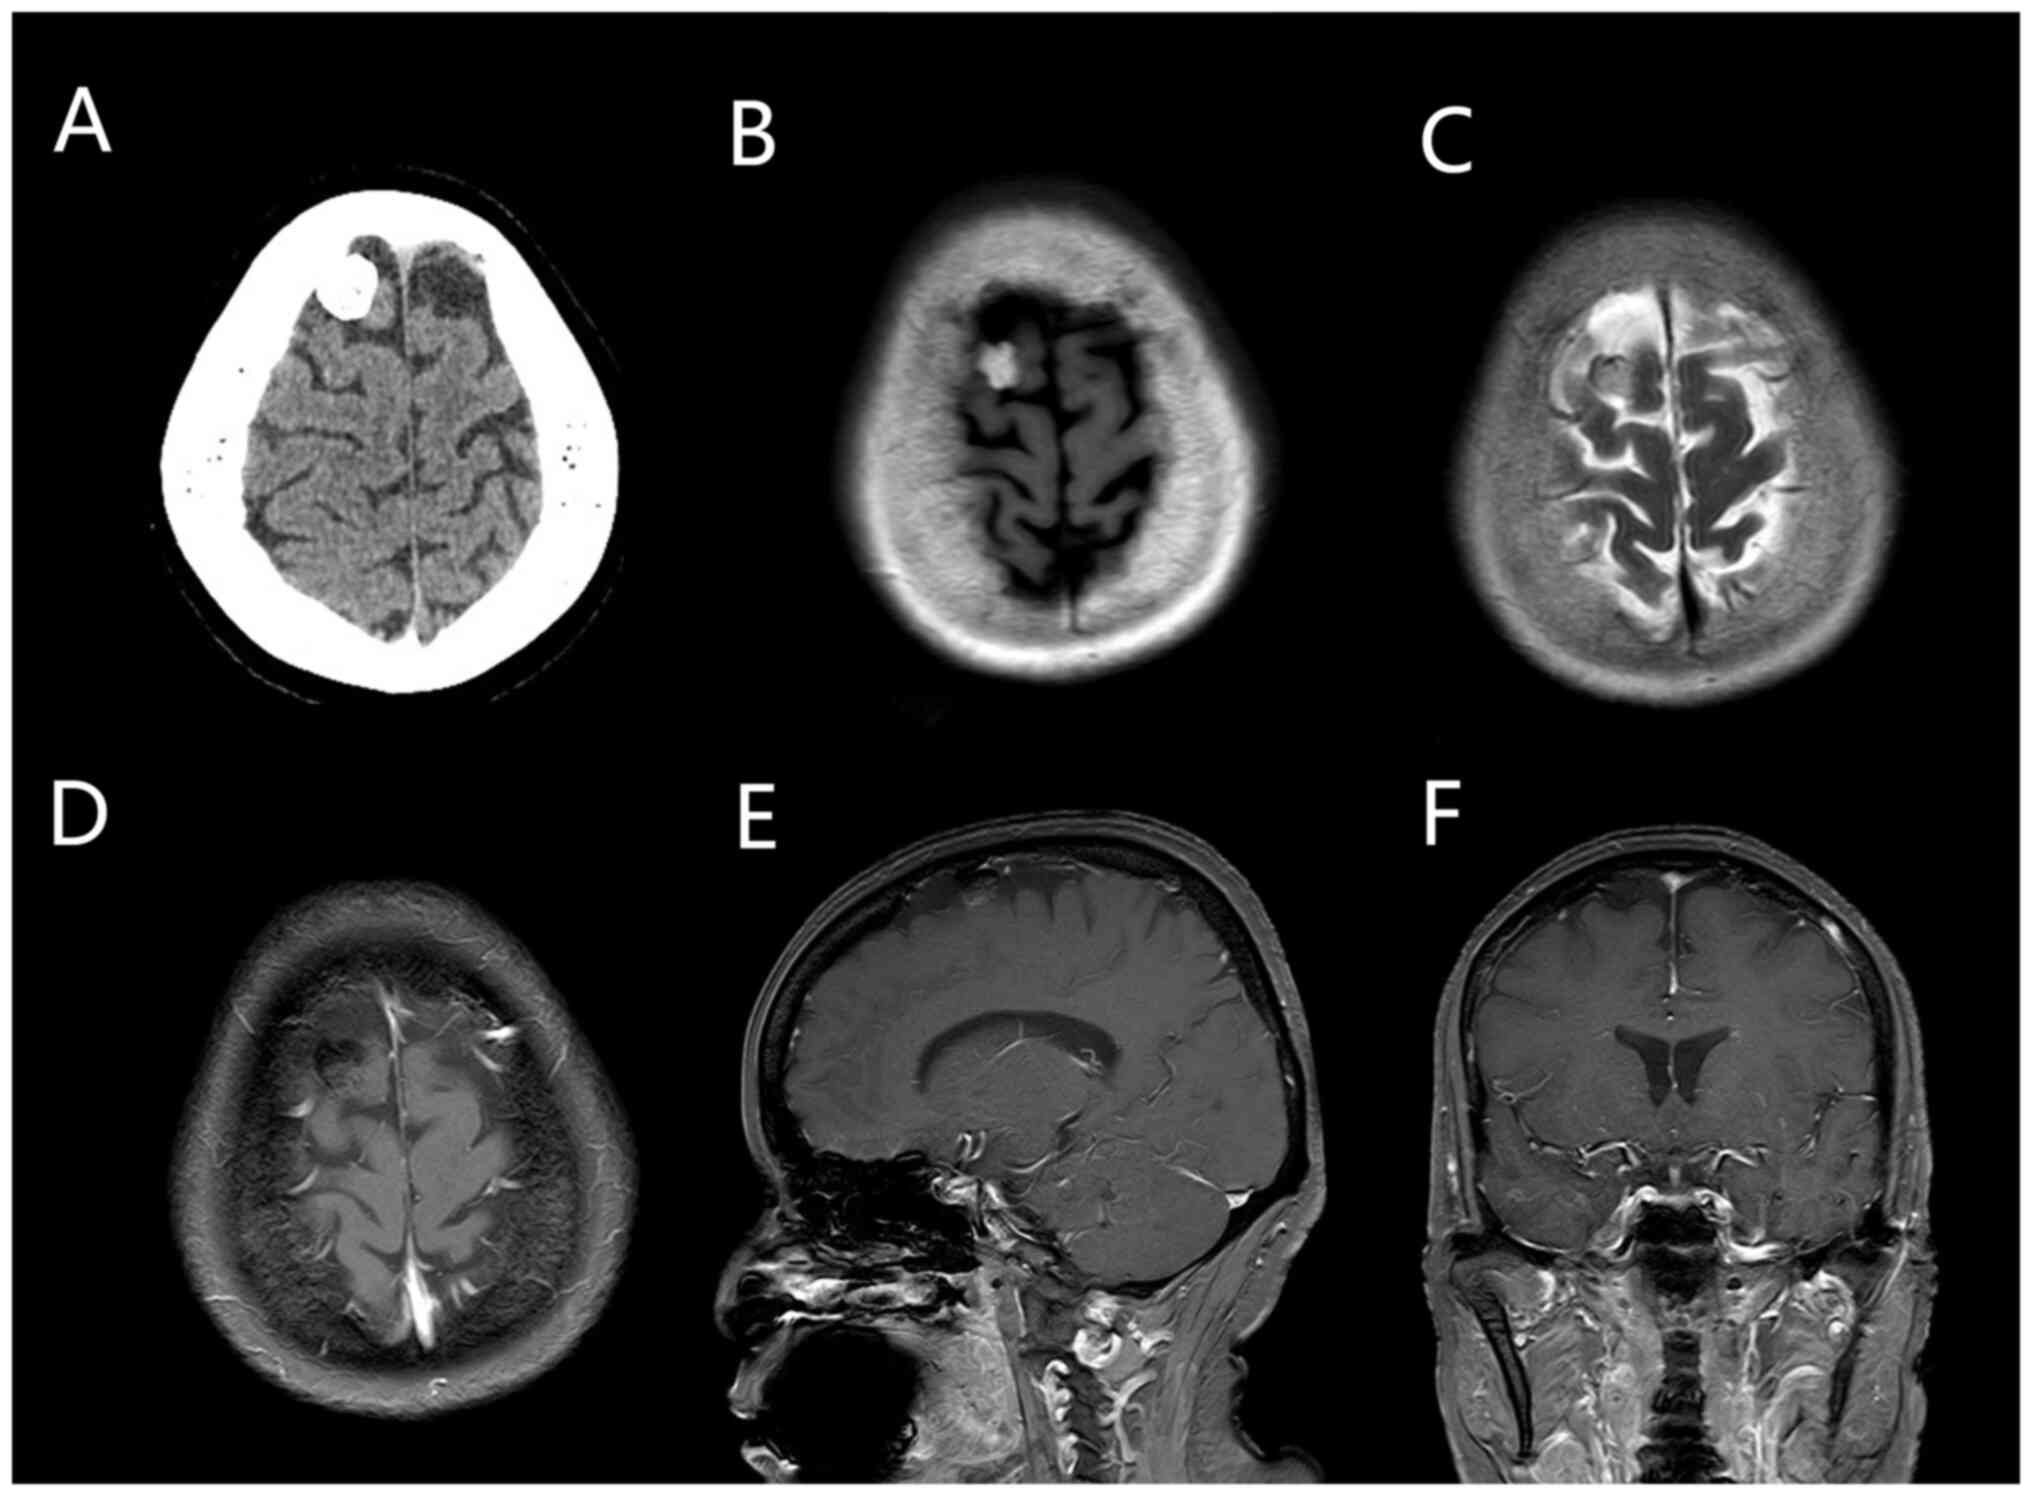

Admission laboratory test results were as follows: Total erythrocyte count 3.81x1012/l, total hemoglobin 117 g/l, total platelet count 270x109/l, total leukocyte count 6.51x109/l, ferritin 55.56 ng/ml, folic acid 50.13 nmol/l and erythropoietin 18 mU/ml. Cranial CT scan results showed a high-density, space-occupying lesion in the right frontal area, possibly an osteoma or calcified meningioma. Thus, magnetic resonance imaging (MRI) was recommended. Cranial enhancement and perfusion MRI revealed an abnormal signal shadow of the nodule in the right frontal area. The size of the lesion was ~1.5x1.2 cm. The T1 image revealed a high signal focus; T2, diffusion-weighted imaging and apparent diffusion coefficient images revealed low signal focus; and the enhancement scan did not show significant enhancement. On perfusion-weighted imaging, the lesion was unclear, indicating the possibility of a meningioma with calcification (Fig. 1).

Figure 1

CT scan showing a high-density quasi-circular shadow with clear boundaries under the inner plate of the skull at the right frontal apex. (A) Enhanced cranial MRI showing the mass presented as a (B) hyper-intense signal on axial T1-weighted imaging and (C) hypo-intense signal on axial T2-weighted imaging. In the T1-weighted MR images, compared with (D) axial, (E) coronal, and (F) sagittal views, no significant enhancement was observed in the enhanced scan. CT, computed tomography; MRI, magnetic resonance imaging.